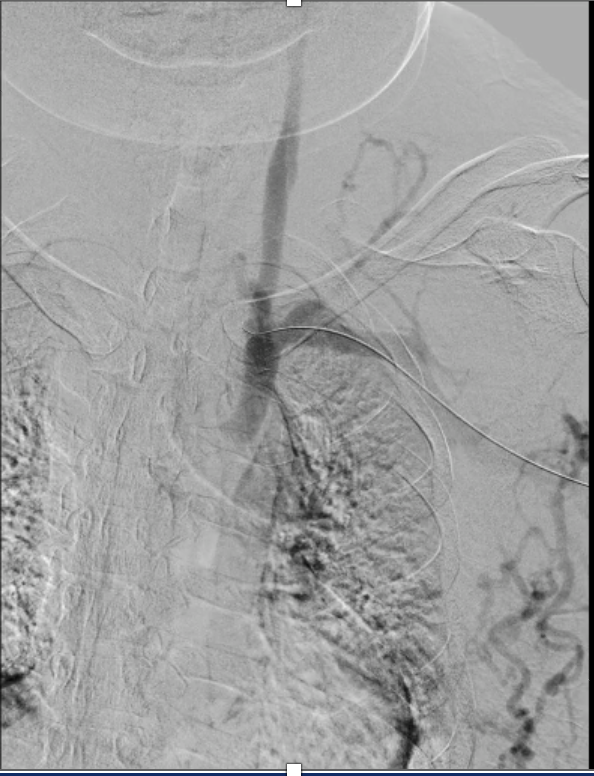

Bilateral venography demonstrated complete occlusion of both brachiocephalic veins with extensive collateral formation.

Real-time echo-guided puncture of both basilic veins was performed, and 6 Fr sheaths were inserted bilaterally. Bilateral venography demonstrated complete occlusion of both innominate veins with extensive collateral formation. A V-18 wire was advanced through the left brachiocephalic vein lesion, followed by a Sterling 5.0 ¡¿ 80 mm balloon inflated to 12 atm from the SVC to the left brachiocephalic vein for angioplasty. The wire was then exchanged for a Connect Flex 0.018¡È ¡¿ 300 cm wire to cross the right brachiocephalic vein lesion toward the internal thoracic connection (ITC). A Sterling 5.0 ¡¿ 80 mm balloon was inflated to 10 atm from the SVC to the right brachiocephalic and right axillary veins for angioplasty; however, the right axillary vein lesion failed to dilate adequately. A Mustang 10 ¡¿ 80 mm balloon was subsequently used and inflated to 20 atm, yet residual stenosis persisted. The wire was exchanged for a Roadrunner wire, and a Conquest 40 balloon was advanced and inflated to 30 atm for high-pressure angioplasty of the right innominate, axillary, and cephalic veins. Subsequently, Wallstent 16 ¡¿ 90 mm was deployed from the SVC to the left brachiocephalic vein, and Wallstent 14 ¡¿ 90 mm was deployed from the SVC to the right brachiocephalic vein. Final post-dilatation was performed using a Mustang 12 ¡¿ 80 mm balloon inflated to 10 atm for both brachiocephalic vein stents.